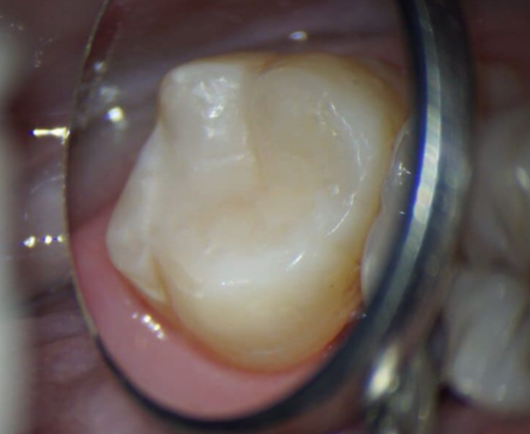

Сокольская Оксана Юрьевна: портфолио (2)